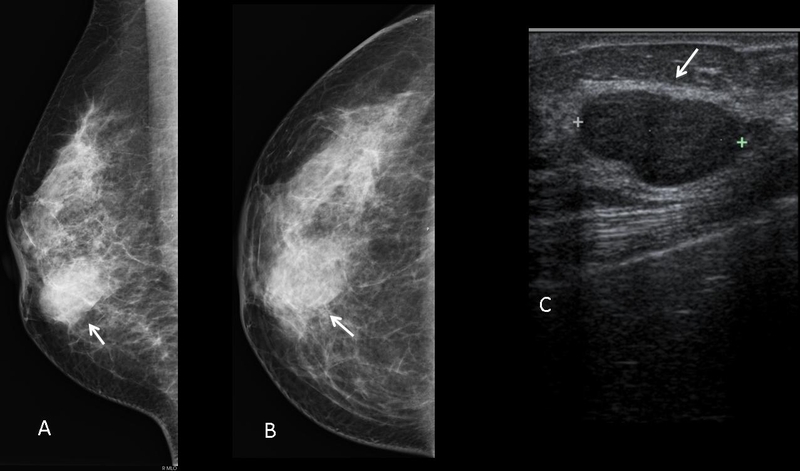

Căn bệnh ung thư vú ngày càng phổ biến, vì vậy khi đi kiểm tra ngực có xuất hiện cục cứng và đau, nhiều người bệnh lo lắng rằng đó có thể triệu chứng của bệnh ung thư vú. Tuy nhiên, hiện tượng nổi cục ở nhũ hoa có thể là do nhiều nguyên nhân khác nhau gây ra chứ không chỉ là khối u ác tính.

Nổi cục ở nhũ hoa có thể là dấu hiệu đầu tiên của bệnh ung thư vú. Tuy nhiên chị em có thể rất dễ bỏ qua do không thường xuyên tự kiểm tra hoặc đi khám khi thấy có dấu hiệu này. Rất khó có thể xác định được u cục ở vú là ác tính hay lành tính nếu như chỉ kiểm tra bằng cách khám tay thông thường, do đó bạn nên chủ động đến bệnh viện để kiểm tra.

Đau tức ngực có thể xuất hiện trước kỳ hành kinh hoặc đang trong giai đoạn thai kỳ. Tuy nhiên, nếu như trong cả ngày bình thường mà bạn thấy xuất hiện những cơn đau dai dẳng, khó chịu thì cần đặc biệt chú ý nên đi kiểm tra sức khỏe. Tốt nhất là bạn nên đi siêu âm vú để kiểm tra xem có xuất hiện u hoặc viêm hay không.